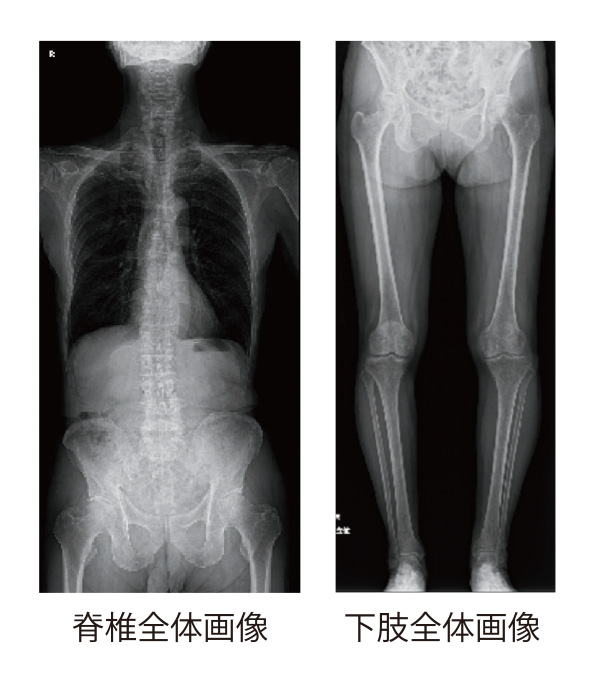

実は、このような技術がレントゲン写真にも利用されていることは、あまり知られていないと思います。レントゲン検査は体にX線を当て、体から出てきた様々な情報を持ったX線を特殊な装置で受けて写真にしますが、その際、撮った写真はその場でパソコンの画面上で確認できますので、まさにデジタルカメラのようなものですね。

実は、このような技術がレントゲン写真にも利用されていることは、あまり知られていないと思います。レントゲン検査は体にX線を当て、体から出てきた様々な情報を持ったX線を特殊な装置で受けて写真にしますが、その際、撮った写真はその場でパソコンの画面上で確認できますので、まさにデジタルカメラのようなものですね。

当院では昨年の7月、最新のX線検査の装置を導入しました。これまでの脊椎全体(首から腰の骨まで)や骨盤から足の先まで撮影する際、数回に分けて撮影する必要があり、検査時間も30分くらいかかっていました。この最新装置では、一回X線を当てるだけで脊椎全体や足全体を検査でき、しかも写真を瞬時にその場で確認できるので患者様の負担も随分少なくなりました。現在では検査時間が短くなり、患者様の待ち時間も大幅に短縮され、サービス改善に大きく貢献しております。検査を行うときに装置のことで気になることがありましたら最寄りのスタッフに遠慮なくお尋ねください。